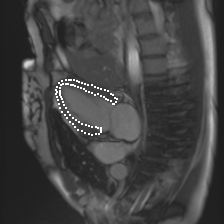

Accurate segmentation and motion estimation of myocardium have always been important in clinic field, which essentially contribute to the downstream diagnosis. However, existing methods cannot always guarantee the shape integrity for myocardium segmentation. In addition, motion estimation requires point correspondence on the myocardium region across different frames. In this paper, we propose a novel end-to-end deep statistic shape model to focus on myocardium segmentation with both shape integrity and boundary correspondence preserving. Specifically, myocardium shapes are represented by a fixed number of points, whose variations are extracted by Principal Component Analysis (PCA). Deep neural network is used to predict the transformation parameters (both affine and deformation), which are then used to warp the mean point cloud to the image domain. Furthermore, a differentiable rendering layer is introduced to incorporate mask supervision into the framework to learn more accurate point clouds. In this way, the proposed method is able to consistently produce anatomically reasonable segmentation mask without post processing. Additionally, the predicted point cloud guarantees boundary correspondence for sequential images, which contributes to the downstream tasks, such as the motion estimation of myocardium. We conduct several experiments to demonstrate the effectiveness of the proposed method on several benchmark datasets.